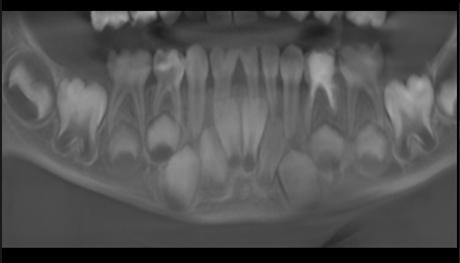

Est. Nicole Emily Rojas Espinoza1 Dr. Juan Pablo Torrico Vilte2

1 Estudiante, Carrera de Medicina, Universidad Privada del Valle. Sede Cochabamba, Bolivia. ren2015280@est.univalle.edu 2Docente, Carrera de Medicina, Universidad Privada del Valle. Sede Cochabamba, Bolivia. jtorricovilte@gmail.com

Recibido:5/1/2023 Revisado:10/5/2023 Aceptado:10/5/2023

Cita: Est. Nicole Emily Rojas Espinoza, Dr. Juan Pablo Torrico Vilte; Cirugía más inmunoterapia local en el tratamiento del tumor de Buschke-Löwenstein. A propósito de un caso. Revista De Investigación E Información En Salud UNIVALLE 2022; 18(44): p.49-53 https://doi.org/10.52428/20756208.v18i44.448

Correspondencia: Est. Nicole Emily Rojas Espinoza, Cochabamba, Bolivia, +591 70797928 ren2015280@ est.univalle.edu

Nota: Los autores declaran no tener conflicto de intereses con respecto a esta publicación y se responsabilizan de contenido vertido.

RESUMEN

El condiloma acuminado gigante o tumor de Buschke-Löwenstein (TBL) pertenece al grupo de carcinomas verrugosos; su agente etiológico se encuentra en los virus del papiloma humano (VPH serotipos 6 y 11), caracterizándose por lesiones verrugosas gigantes de localización perineal. Presentamos el caso de un paciente masculino de 28 años diagnosticado con condiloma gigante de Buschke-Löwenstein, se realizó tratamiento quirúrgico agregando imiquimod tópico como terapéutica adyuvante con excelente evolución a largo plazo.

Palabras Clave: Condiloma acuminado gigante, Tumor de Buschke-Löwenstein, Virus del papiloma humano

ABSTRACT